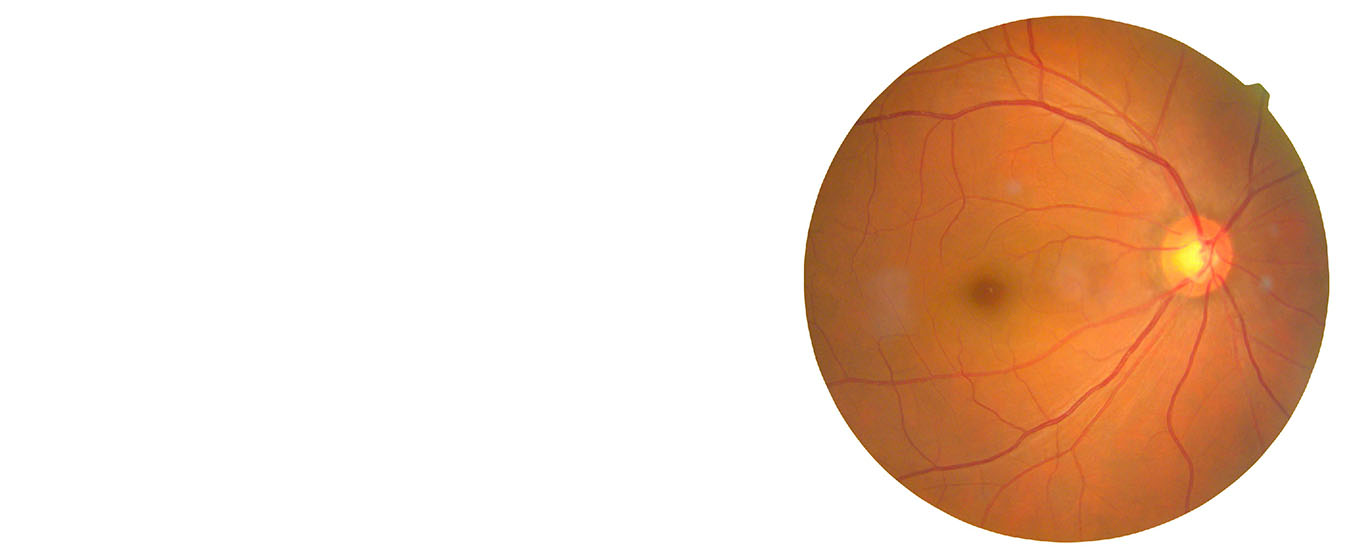

Hypertensive retinopathy is a medical condition characterized by damage to the blood vessels in the retina due to high blood pressure. Prolonged and uncontrolled hypertension can lead to changes in the retina's small blood vessels, causing them to narrow, leak, or become blocked. This can impair blood flow to the retina and cause Hypertensive Retinopathy. There are a lot of treatment methods available for hypertensive retinopathy in Ayurveda. Regular eye examinations are essential for early detection and management of hypertensive retinopathy to prevent further damage to the retina and preserve vision. In addition, controlling blood pressure through lifestyle modifications and Ayurvedic medications is crucial in managing this condition.

Grade 3: Upon examination, retinal damage becomes evident, including signs such as retinal haemorrhage (bleeding) and the presence of cotton wool spots—white patches on the retina. Symptoms may start to manifest at this stage.

Grade 4: Severe hypertensive retinopathy that includes the characteristics of Grade 3, along with swelling of the optic disc (papilledema). Symptoms are usually present, indicating a more advanced stage of the condition.